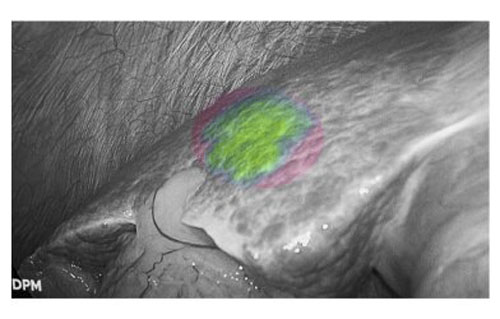

荧光显影技术,可精确显示肝内隐匿病灶

患者肝右后叶肝癌,根据三维重建精准阻断右后肝蒂,获得缺血线后进行荧光反染,显示肝脏切面的荧光和非荧光界面,助力解剖性肝右后区切除。